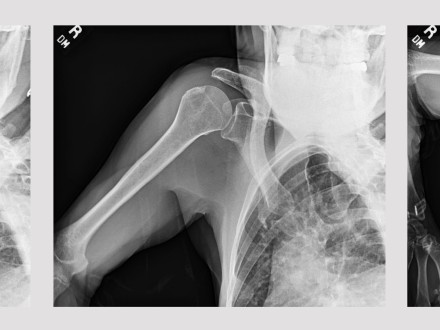

Wayne, NJ, October 14, 2022 – Konica Minolta Healthcare Americas, Inc., congratulates the Emory Healthcare researchers that won two awards at the 2022 Orthopedic Research and Education Foundation (OREF) Eastern Region Resident Research Symposium for the presentation, “Artificial Intelligence Automated Analysis of Scapula Dynamics using Dynamic Digital Radiography: An Initial Reliability Study.” Zaamin B. Hussain, MD, an orthopedic surgery resident working with Eric Wagner, MD, MSc, Director of Upper Extremity Research and Assistant Professor at Emory Healthcare, received a Second Place Award and the Presenter’s Choice Award. Next, he will present his research at the National OREF Symposium later this year.

Dr. Hussain’s research evaluated a prototype artificial intelligence (AI) tool developed by Konica Minolta Healthcare for characterizing shoulder dynamics. Seventy-three shoulders (23 normal controls, 41 rotator cuff tears and nine adhesive capsulitis) were imaged using Dynamic Digital Radiography (DDR) and reviewed by two trained readers.

With the DDR image data, Dr. Hussain was able to visualize changes in shoulder pathology and, using the proof-of- concept AI tool, acquire measurements to calculate the scapulohumeral rhythm (SHR). SHR measurement is a time- consuming manual process for calculating the scapulohumeral ratio and evaluating function of the shoulder joint. The new AI tool employs a machine learning algorithm utilizing a convolutional neural network architecture to automate this analysis. Dr. Hussain's research demonstrated that the AI tool has good reliability (ICC 0.58 (95% confidence interval 0.4- 0.71)) between manual and AI measurements of SHR.

“We demonstrated the early promise of this AI tool, which may allow for a more rapid measurement of the SHR and enable automated image analysis and diagnostics in shoulder pathology,” says Dr. Hussain. “DDR provides the best of two worlds – it allows us to dynamically visualize the shoulder while it is in motion and enable quantitative measurement of shoulder anatomy in motion, the gold standard for discerning changes in joint anatomy. Further enhancing the prototype AI tool could lead to a more efficient integrations of SHR measurements in clinical workflow and increase the clinical utility of DDR in a clinical setting.”

“One of the really exciting things about DDR is the ability to see what is happening with a patient’s joints from a way that we’ve never been able to see before,” says Dr. Wagner. “In patients with limited range of motion, I can identify the point at which the patient is having difficulty and see the source of the limitations. These insights are especially useful in treatment decisions and pre-surgical planning. For example, in the shoulder, using DDR we can differentiate the limitations in the shoulder vs shoulder blade motion, potentially improving our diagnostic and therapeutic algorithms. New tools that help quantify how structures move in relation to one another only adds to our knowledge of the individual patient so we can deliver the best possible outcome. Although this work and collaboration has already resulted in national and international presentations, publications, and research awards, we are only seeing the top of the iceberg with this technology.”